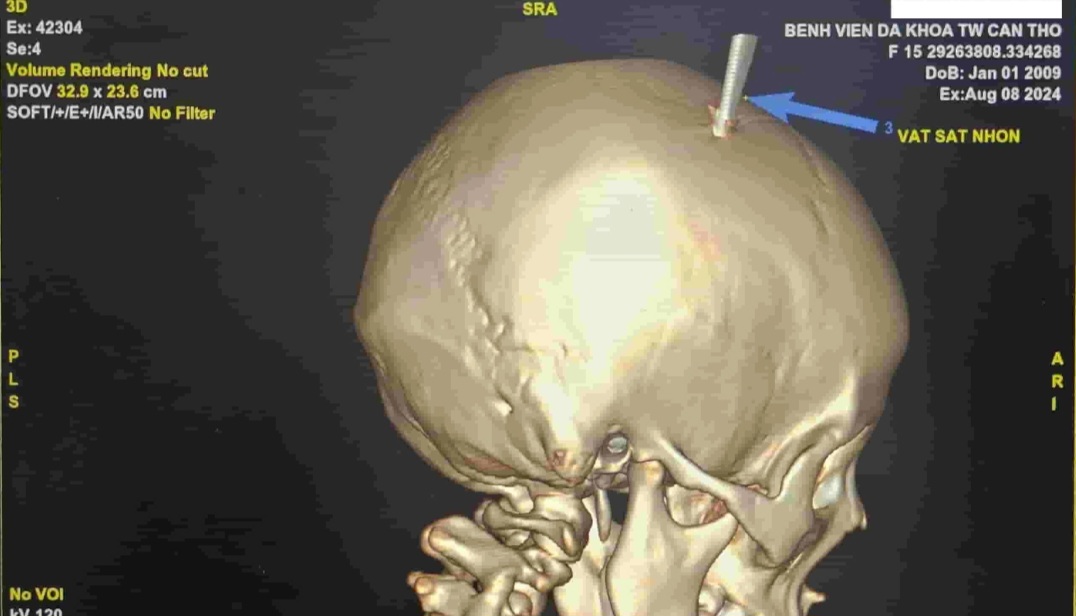

Successful emergency care for a male student whose key was stabbed in the skull

108 Central Military Hospital has just successfully received and operated on a male student with a traumatic brain injury due to a key stuck through the skull.

Immediately upon receiving the patient, the doctors quickly conducted an examination, CT scan and performed the necessary tests to assess the damage. After consultation, the patient was indicated for emergency surgery to remove the foreign object from the head area.

Colonel, Dr. Do Khac Hau - Deputy Head of the Neurosurgery Department, 108 Central Military Hospital said: The surgery was successful, helping to completely remove the foreign object without causing more serious damage to the patient. In particular, the wound is close to the transverse vein Tube, if the lesion only deviates by a few millimeter, the patient may be in danger of death due to the lesion causing bleeding.